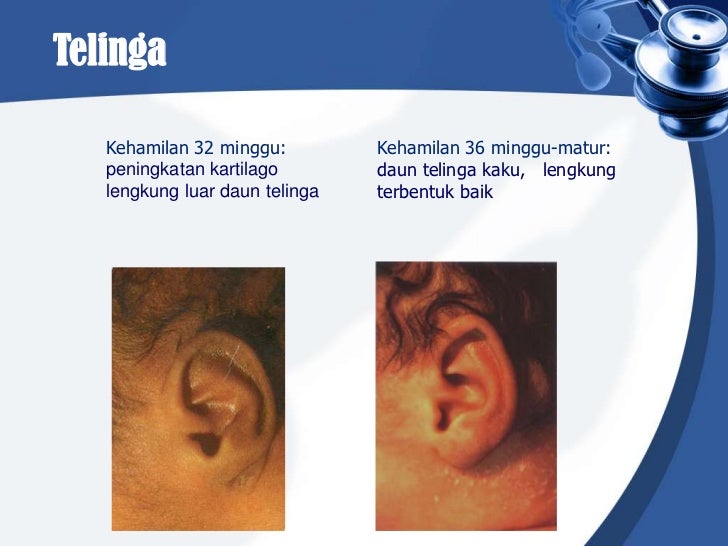

Menentukan Periode Dan Usia Kehamilan Ppt Download

Menentukan Periode Dan Usia Kehamilan Ppt Download

Menentukan Periode Dan Usia Kehamilan Ppt Download

Menentukan Periode Dan Usia Kehamilan Ppt Download